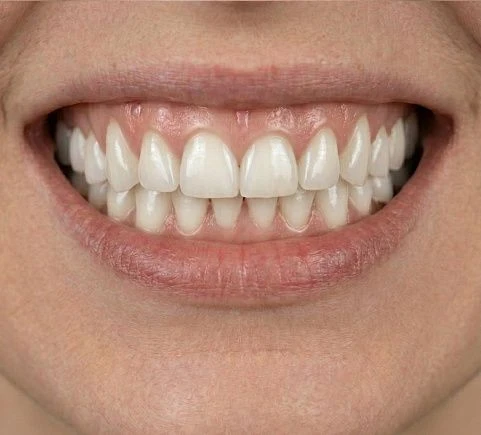

Будет ли заметна разница между Е-max и натуральными зубами при улыбке?

Наши специалисты внимательно подходят к подготовке и подбирают оттенок коронки, идеально повторяющий натуральную эмаль пациента. При правильном изготовлении и установке отличить искусственную коронку от натурального зуба невозможно, и удается полностью восстановить эстетику улыбки.

Наши работы